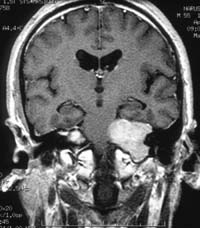

<¾È¿ÍºÎ

³ú¼ö¸·Á¾>

<¼ö¼ú

Àü>

<¼ö¼ú ÈÄ>

¿ìÃø

½Ã·Â°¨¼Ò¿Í ¾È±¸¿îµ¿Àå¾Ö¸¦ º¸ÀÌ´ø ȯÀÚ¿¡¼

¹ß°ßµÈ ¾È¿ÍºÎ ¼ö¸·Á¾ ³úMRI ¼Ò°ß(¼ö¼úÀûÄ¡·á·Î

ÀüÀûÃâµÇ¾ú´Ù)